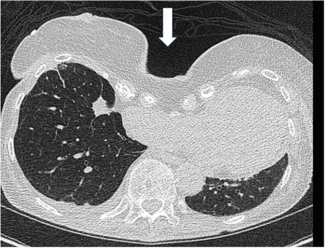

Dr. Kern and his expert colleagues discuss a case of pectus excavatum, a structural deformity of the anterior thoracic wall in which the sternum and rib cage produce a caved-in or sunken configuration of the chest. It can be congenital at...